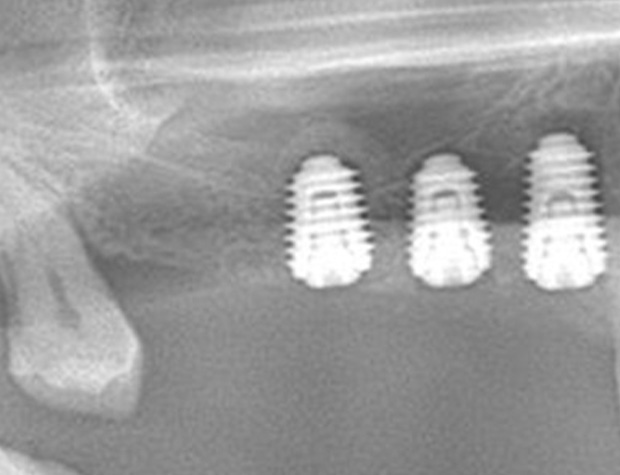

Implantologische Fälle schnell und einfach lösen ist der Wunsch eines jeden Implantologen. Die Realität ist allerdings eine andere. Diverse Knochendefekte, schlechte Knochenqualität, Weichgewebsdefizite und viele weitere schlechte Grundvorraussetzungen existieren und machen jeden Eingriff zu einer Herausforderung. Um solche implantologischen Fälle dennoch erfolgreich zu therapieren, benötigen Sie einfach handhabbare Techniken, die schnell zu erlernen sind und nahezu jeden Fall realisierbarer gestalten kann. Die Osseodensifikation ist eine Technik die schnell und einfach zu erlernen ist und viele Möglichkeiten Ihnen bietet. Das Implantatbett bei schlechter Knochenqualität optimal aufbereiten ist bereits bekannt, aber einen Kieferkamm spreizen oder sogar einen Sinuslift vorhersagbar durchzuführen, ohne die Schneider’sche Membran zu perforieren, das sind die Optionen, die Sie schnell und einfach erlernen können. Um Ihr Portfolio noch zu erweitern, wird die GBR-Technik mittels moderner Materialien Ihnen beigebracht.